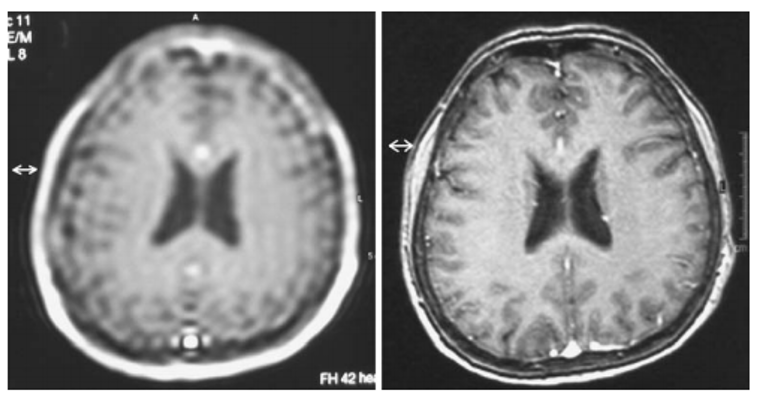

How can Gibbs artifact be minimized

Truncation errors (Gibbs artifact) can be minimized by increasing the number of phase-encode steps or by reducing the field of view.

What was the most likely step taken to eliminate the artifact seen in the first image?

Increasing the matrix size decreased truncation artifact (aka Gibbs, or ringing).

choosing a smaller FOV can also help eliminate this artifact